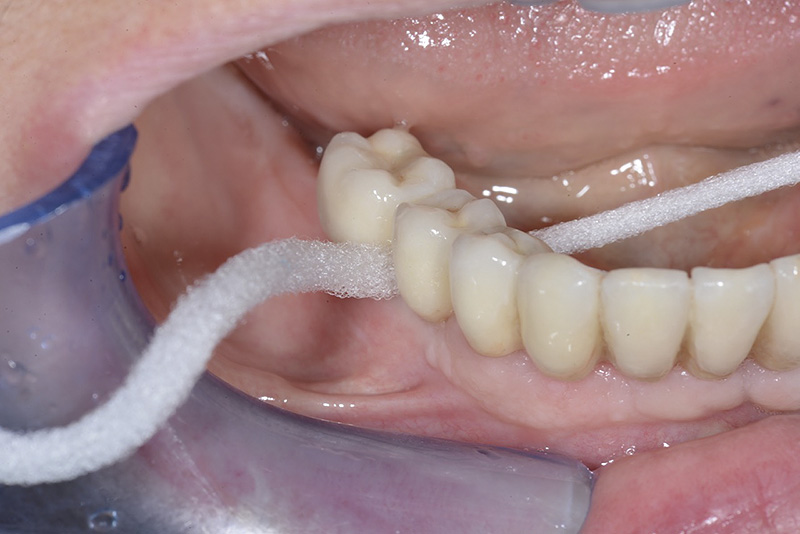

Vengono utilizzati 2 tipi di provvisori: il primo, cementato ai denti vicini, viene utilizzato dal momento dell’estrazione del dente fino ad impianto osteointegrato (circa 6 mesi); il secondo, avvitato direttamente all’impianto, ha una funzione di prova estetica ma soprattutto di guida per la maturazione dei tessuti gengivali peri-implantari portandoli verso la maturazione completa prima di posizionare la corona finale in disilicato di litio.